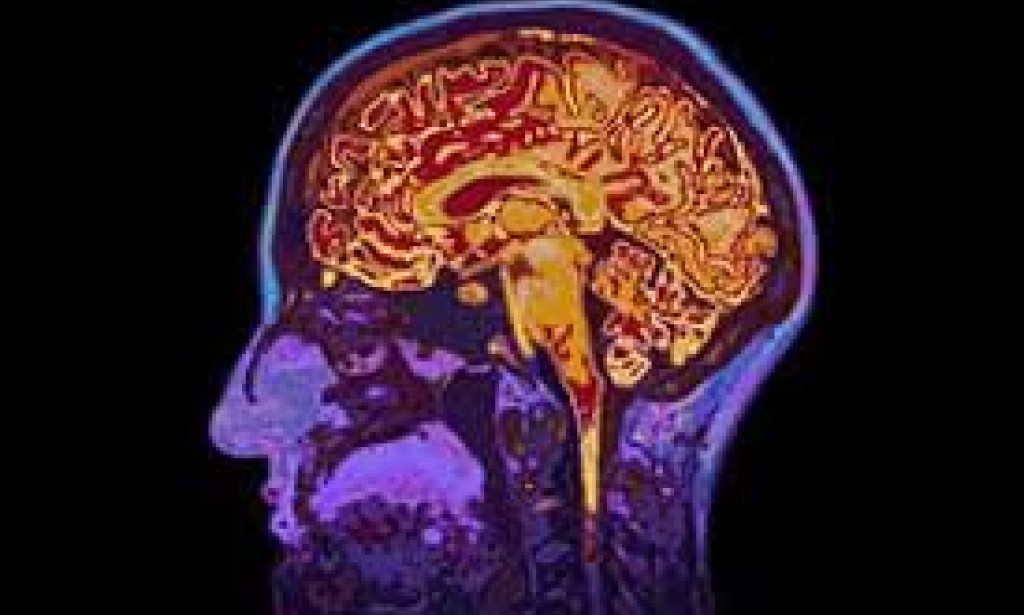

Mental Health Disorders – Abuse can lead to depression, anxiety, and addiction.